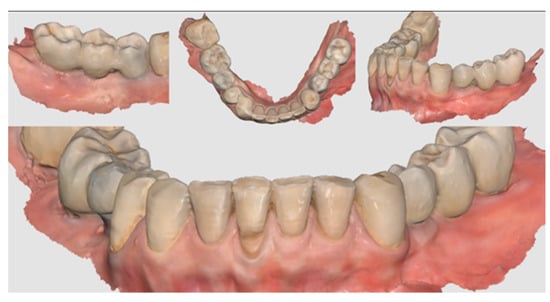

Figure 11.

Scan taken after 18 months of prosthetic loading.